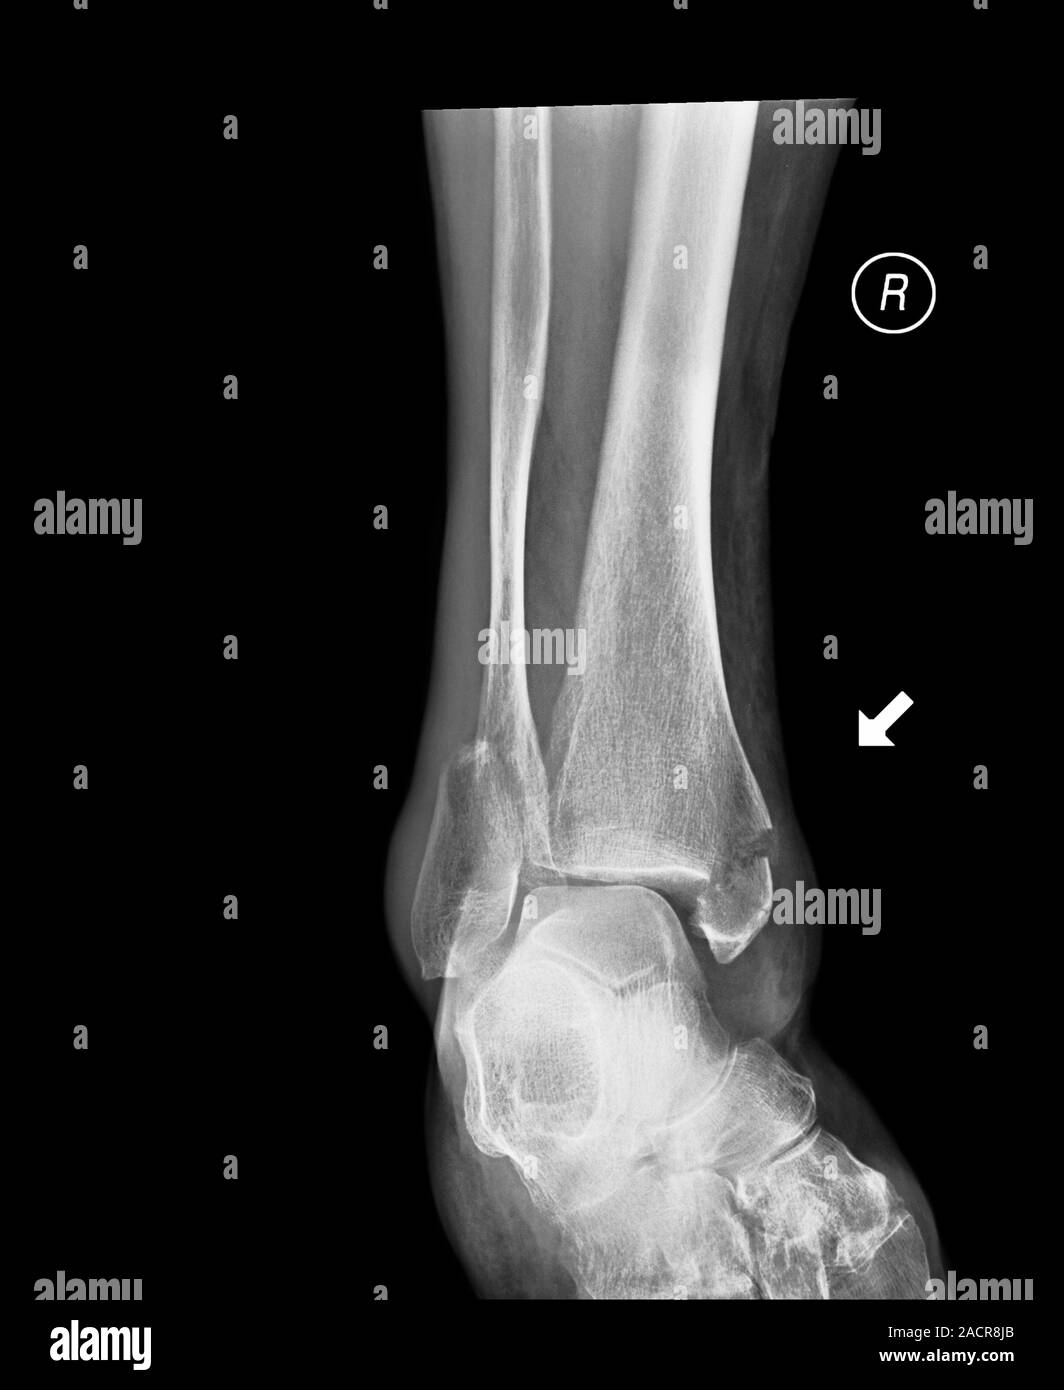

Fractured ankle. Xray of a section through the right ankle of a 13 Calf In Bone Fracture A broken leg is a bone fracture (broken bone) in your leg. A broken leg (leg fracture) is a break or crack in one of the bones in your leg. Common causes include falls, motor vehicle accidents. A fracture, or break, in the shinbone just below the knee is called a proximal tibia fracture. The fibula, or calf bone, is. Calf In Bone Fracture.

Broken ankle. Xray of the lower leg of an 85 year old female with Calf In Bone Fracture Here, health care providers typically evaluate the injury and immobilize the leg with a splint. There are three bones in your leg, including. A broken leg is a bone fracture (broken bone) in your leg. Treatment can vary, but often involves aligning the. What is a broken leg? A broken leg (leg fracture) is a break or crack in one. Calf In Bone Fracture.